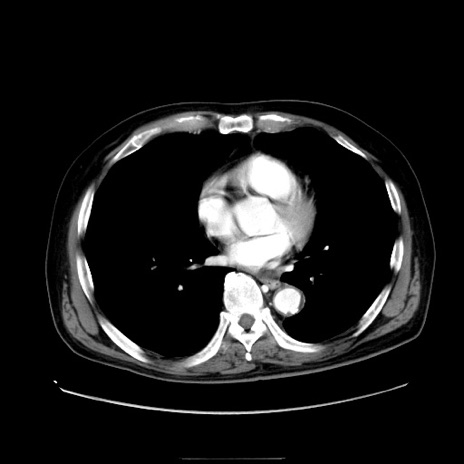

症例30(横断像)

【症例】80歳代男性

【主訴】臍周囲痛

【現病歴】約6時間前から臍下部痛が出現。次第に腹部膨隆・背部痛も生じてきたため来院。背部痛の場所は変化しない。

【身体所見】意識清明、BT 36.3℃、BP  131/87mmHg、P 87bpm、SpO2 100%(RA)、臍周囲自発痛・圧痛あり、反跳痛なし、自発痛部位に一致して板状硬あり、腹部膨隆、腸雑音減弱、CVA tenderness両側陰性。

【データ】WBC 19600、CRP 0.33